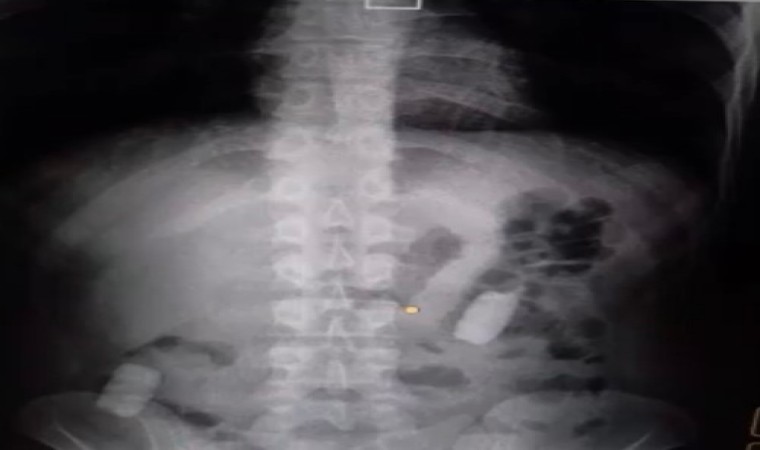

Kayseri İl Emniyet Müdürlüğü Narkotik Suçlarla Mücadele Şube Müdürlüğü ekipleri, uyuşturucu madde ticareti yapan şahıslara yönelik analiz çalışması yürüttü. M.R.B’nin (23) kente uyuşturucu madde getireceğini tespit eden ekipler operasyon düzenledi. Gözaltına alınan şahsın hastanedeki iç beden muayenesinde 77 adet kapsül şeklinde 1 kilo 134 gram narkotik madde ele geçirildi. Şahsın midesindeki maddeler cerrahi müdahale ile çıkarılırken, şahıs hakkında "uyuşturucu madde ticareti yapmak" suçundan adli işlem başlatıldı.